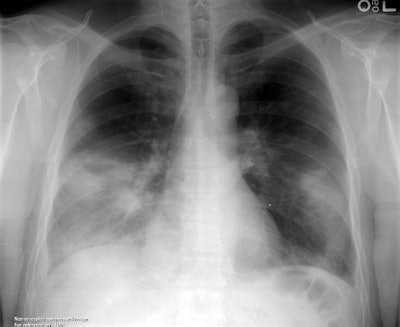

The patient was an itinerant homeless male who had killed and skinned a wild rabbit. During the skinning, the patient had cut his hand. The patient subsequently presented with fever, cough, and some shortness of breath. The patient denied any history of painful adenopathy, although enlarged axillary nodes were detected on physical exam. The chest radiograph demonstrated bilateral lower lobe infiltrates and bilateral effusions which were found to be exudative.